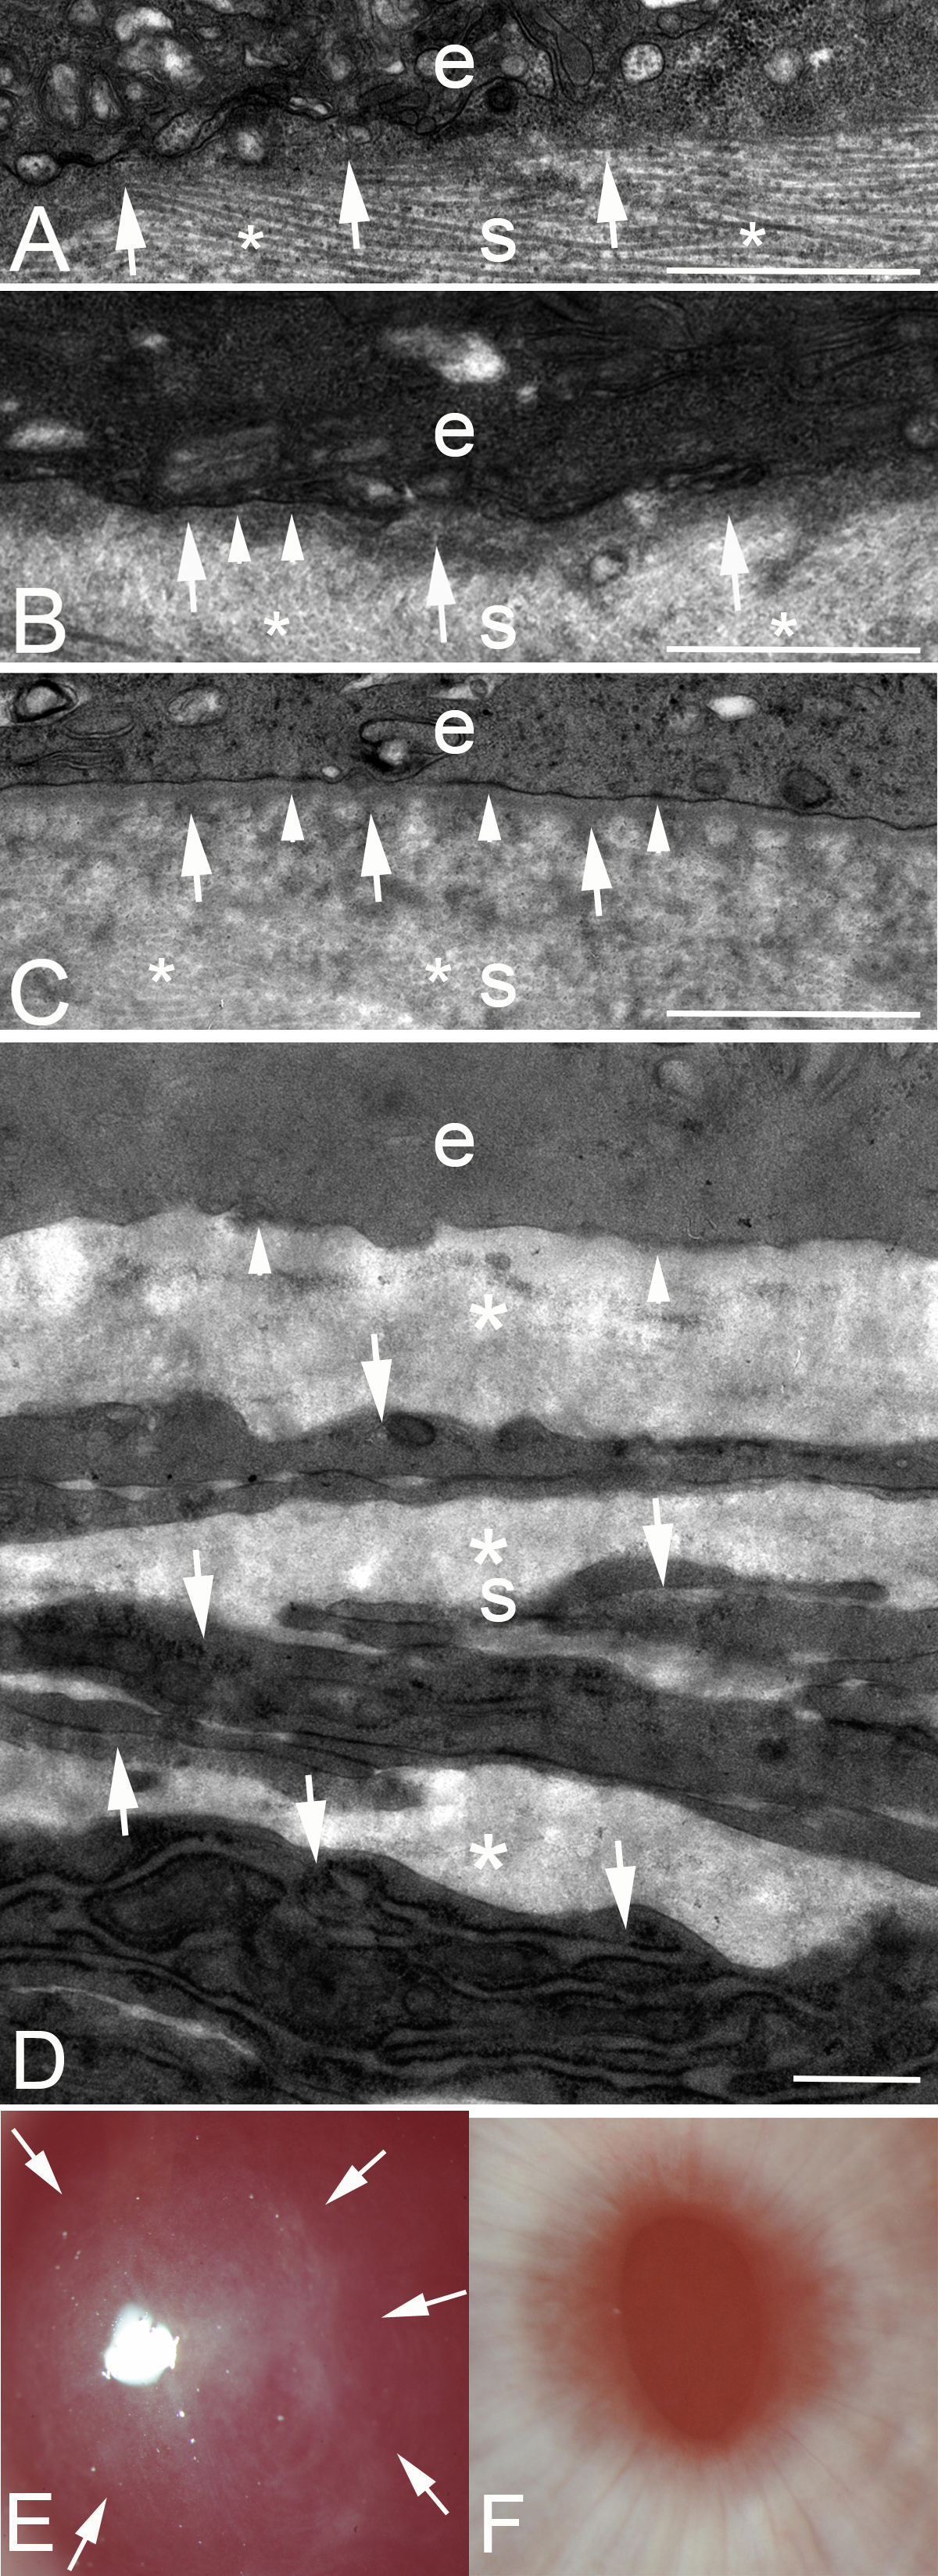

Figure 1. Transmission electron microscopy of the junction between the epithelium and the stroma at different time points after low-correction −4.5D photorefractive keratectomy (PRK) or high-correction −9.0D PRK in rabbits. e, epithelium; s, stroma. A: In a cornea at 7 days after −4.5D PRK, no discernable lamina lucida or lamina densa is present. Note, by chance, the specimen was cut such that the stacked collagen lamellas (*) are seen in the stroma. Dense deposits of extracellular matrix (arrows) can be seen in the stroma just posterior to the epithelium. Magnification = 23,000X. B: In a cornea at 8 days after −4.5D PRK, most of the excimer laser-ablated zone had no lamina lucida or lamina densa. However, in one area (arrowheads) nascent lamina lucida and lamina densa can be noted. Again, dense extracellular matrix seen in the stroma just posterior to the epithelium. In the stroma, collagen lamellas (*) that have been cut transversely can be noted. Magnification = 23,000X. C: In a cornea at 9 days after −4.5D PRK, there is a complete lamina lucida and lamina densa (arrowheads) across 100% of the excimer laser-ablated zone. Again, the dense extracellular matrix is noted just posterior to the intact epithelial basement membrane (EBM). In the stroma, collagen lamellas (*) that have been cut transversely can be noted. D: In a cornea at 1 month after −9.0D PRK that developed severe stromal fibrosis (haze), no normal EBM is detected beneath the epithelium (arrowheads). The anterior stroma is filled with stacked myofibroblasts (arrows) with large amounts of intracellular rough endoplasmic reticulum and surrounding disorganized extracellular matrix (*) that are the alpha-smooth muscle action+ (α-SMA) cells noted in Figure 2A. Magnification = 23,000X. E: Slit-lamp photograph of a rabbit cornea at 1 month after −9.0D PRK. Note the dense haze (arrows) in the central excimer laser-treated cornea with the pupil dilated. Magnification = 40X. F: Slit-lamp photograph of a rabbit cornea at 1 month after −4.5D PRK. Note the cornea is clear without fibrosis, and thus, the iris details are clear. Magnification = 40X. Scale bars (AD) = 2 µm.